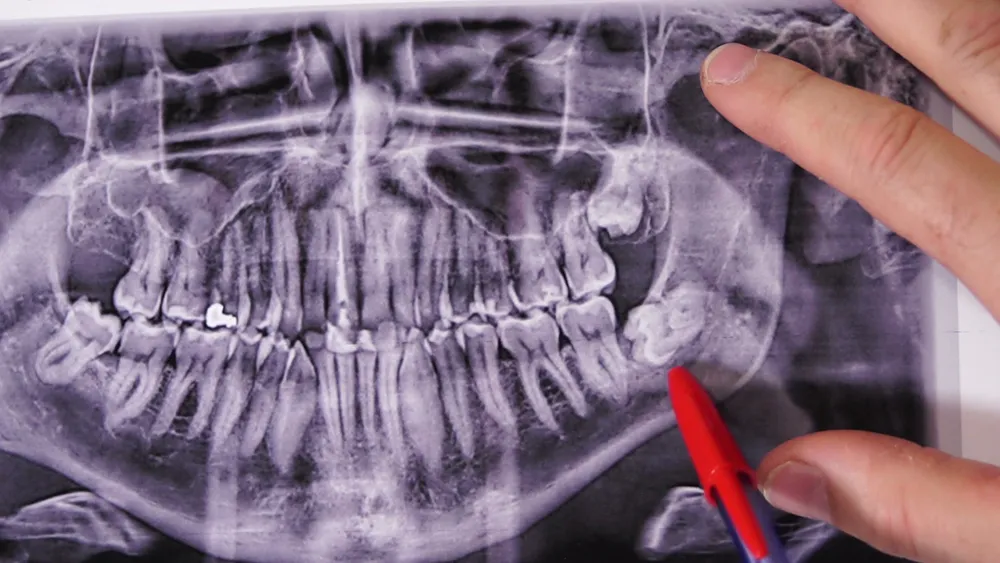

- 시설과 장비: 치과의 시설과 장비가 최신식인지 확인하세요. 최신 장비를 사용하는 치과는 더 정확하고 안전한 시술을 제공할 수 있습니다.

- 최신 기술 도입: 최신 임플란트 기술과 장비를 도입하여, 보다 안전하고 효과적인 시술을 제공합니다.